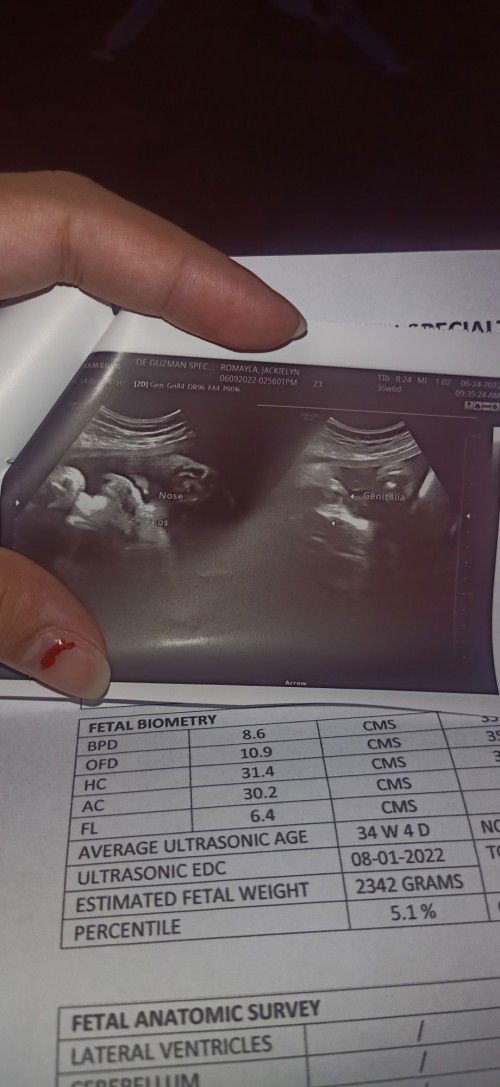

Mga mi ok lang po kaya 37wks and 2dys nako pero ang estimated weight ni baby 2342g? Worried po ako😌

Pa help mga mi paano kopo mapapataas ng konti weight ni baby 2342g palang sya 37 weeks na ako buks🥺